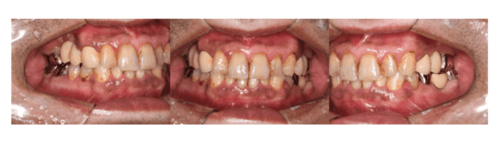

症例3

治療前

治療後(約1週間後)

| 年齢・性別 | 39歳・男性 |

|---|---|

| 主訴 | 上下前歯唇側歯肉の歯肉の色が気になる |

| 治療内容 | 上下顎ガムピーリング |

| 治療費 | 11,000円(2023年2月現在) |

| 治療期間 | 1回30分 |

| リスク・副作用 | ・薬剤の効果により一時的に歯肉が白くなります ・個人差はありますが術後ヒリヒリとした痛みを感じることがあります ・フェノール・アルコール類のアレルギーがある方は行えません ・生活習慣によっては後戻りする可能性があります ・効果には個人差があり色素沈着が深部に浸透している場合は回数がかかることがあります |

| 担当者所見 | タバコをやめたことをきっかけに歯茎を綺麗にしたいと来院されました。 特に下顎右側は長年の喫煙の影響で暗黒色になっており、深部までの沈着は1度ではとりきれないことが予想されました。 しかしピーリング後1週間の状態を見ると、かなり薄色化しており患者様も結果に満足してくださったので1度で終了し今後経過を見ることになりました。 歯茎が綺麗になったことがきっかけでホワイトニングにも興味を持ってくださり今後は歯のクリーニング・ホワイトニングを行なっていく予定です。 |